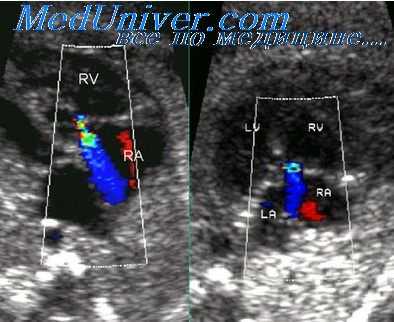

е) Цветовая допплерография. С помощью допплеровского картирования можно выявить клапанный или подклапанный стеноз легочного ствола и оценить эффективность операции бандирования по появлению турбуленции кровотока.

ж) Спектральная допплерография. С помощью спектральной допплерографии при врожденной обструкции выносящего тракта желудочка можно определить градиент давления в нем и рассчитать систолическое давление в легочном стволе. Данное исследование позволяет также оценить эффективность операции бандирования легочного ствола.

Единственный желудочек при сканировании из апикальной четырехкамерной позиции. Оба предсердия разделены межпредсердной перегородкой, оба атриовентрикулярных клапана расположены в каудальной части межпредсердной перегородки. Они открываются в общий желудочек (V), верхушечная часть которого обозначена звездочкой. Состояние после хирургического сужения легочного ствола (МРА) с помощью синтетической полоски (бэндинга), которая обозначена на эхокардиограмме двумя стрелками. На этом же уровне отмечается турбулентный кровоток. При столь неблагоприятном угле расположения допплеровского датчика определить точно максимальную скорость кровотока по спектральной кривой невозможно (спектральная допплерография в непрерывноволновом режиме).